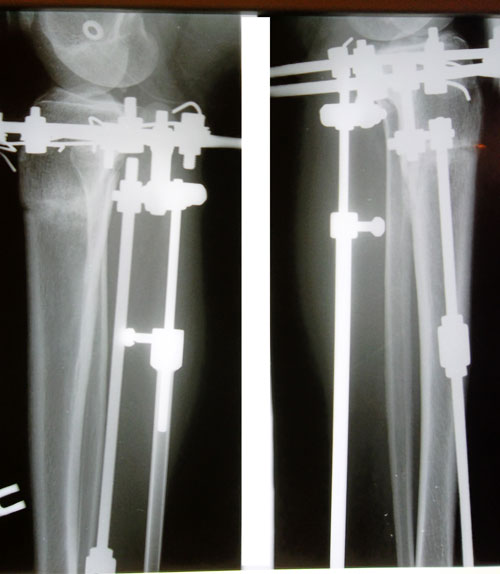

В процессе исправления.